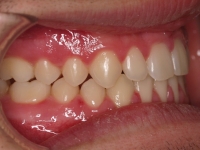

Chica de 17 años tratada en 1 año con stripping en los dientes inferiores